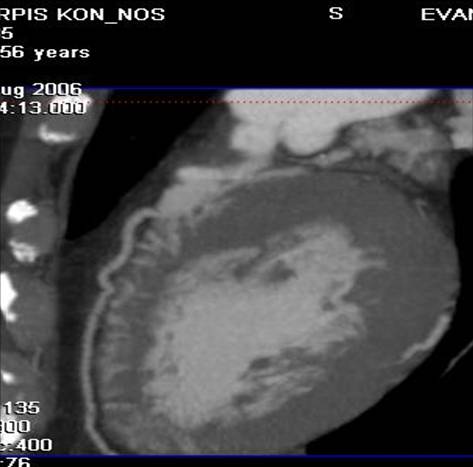

The non-invasive imaging modality of multi-detector computed tomography has dramatically evolved the last ten years and that is due to hardware and software developments. The newer generation of scanners allows increased spatial and temporal resolution that improves the clinical reliability giving further insights into the evaluation of coronary artery disease. Heart morphology imaging followed by studies of myocardial function and assessment of cardiac valves can be performed from the information derived from the data of the coronary artery examination. Also, the venous anatomy of the heart, coronary artery bypass grafts, stents, and cardiac tumors can be imaged and evaluated when necessary. For the beneficial use of this method, entrance criteria for different patient groups need to be set in order to allow improved outcome of multi-detector CT.